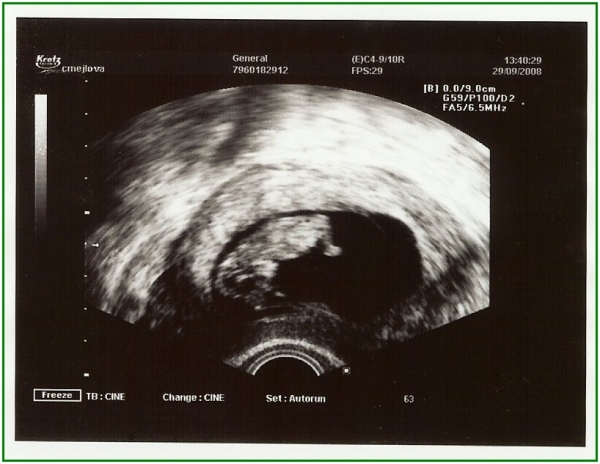

Pod pokličkou poprvé

Pod pokličkou podruhé